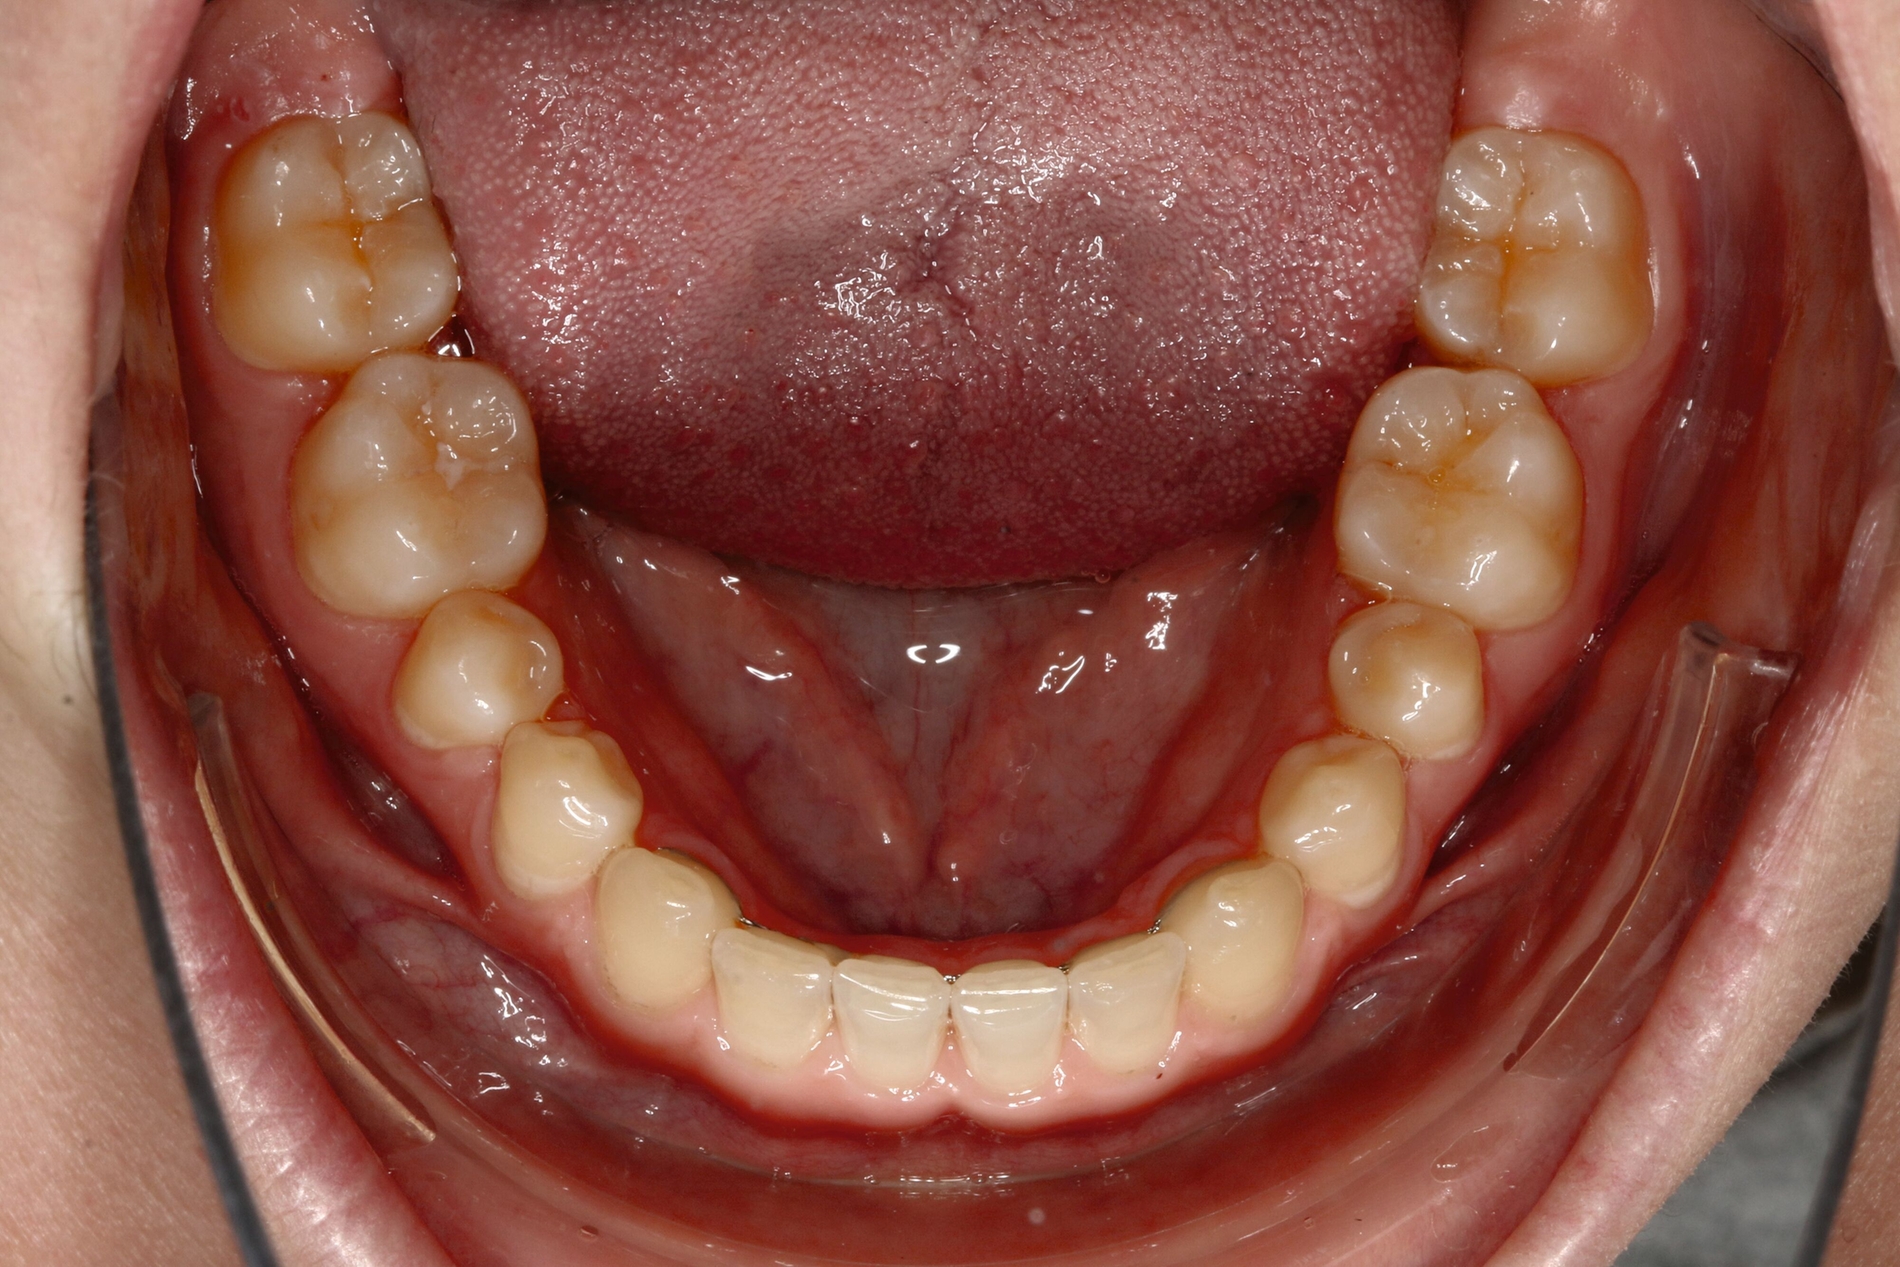

Bei dem gut zwölfjährigen Mädchen sind die seitlichen oberen Schneidezähne (Zähne 12 und 22) nicht angelegt. Zusätzlich zeigten sich verlagerte zweite obere Prämolaren.

Im vorliegenden Fall stand der Zahn 23 bereits im Mesialstand bei hoher Lachlinie und tendenziell konkavem Lippenprofil. Bezüglich Morphologie und Farbe waren die Zähne 13 und 23 nicht ausgeprägt eckzahntypisch. Es bestand kein Platzmangel im Gegenkiefer. Die Patientin war bei der Erstdiagnose 12,5 Jahre alt und im Wechselgebiss der zweiten Phase mit atypischer Durchbruchreihenfolge. Es bestand eine geringfügige Klasse II. Der Overjet war vergrößert bei vertikaler Wachstumstendenz, der Overbite war um circa einen Millimeter vergrößert aufgrund der geringfügigen Steilstellung der Oberkiefer-Front. Es bestand der Verdacht auf Nichtanlage der Weisheitszähne, 15 und 25 waren verlagert.